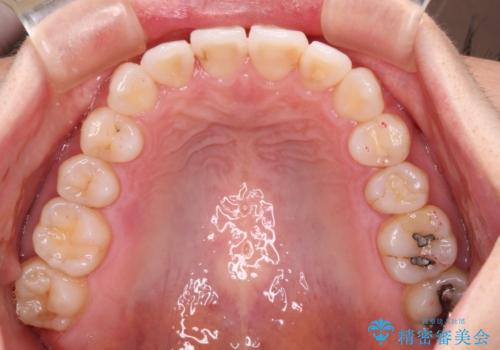

- ワイヤーではない矯正治療があると聞いたとのことで来院された患者様です。

長年前歯のデコボコを気にしていたもののワイヤー矯正に抵抗があり躊躇していたそうですが、インビザラインなら治療してみたいとのことで相談にいらっしゃいました。

インビザライン適用の歯列であったため、歯と歯の間を削るIPRを用いて改善することとしました。